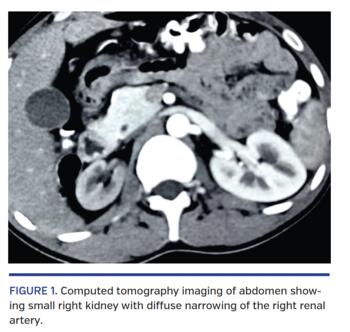

A 20-year-old man presented with a severe headache and sudden-onset blurring of vision of 2-month duration. Fundus examination revealed hypertensive retinopathy in both eyes. His blood pressure was 190/120 mm Hg, for which amlodipine, telmisartan, and diuretics were started. Systemic examination was unremarkable. Routine serum biochemistry was normal; serum creatinine was 0.88 mg/dL and estimated glomerular filtration rate was 87 mL/min/1.73 m2. Ultrasound revealed small right kidney (5.8 x 3.4 cm) and normal-sized left kidney (9.4 x 4.3 cm). Computed tomography scan of the abdomen confirmed small right kidney and diffuse non-ostial narrowing of the right renal artery (Figure 1). Various serum tests for autoimmune and procoagulant work-up were negative. Echocardiogram was normal, with no evidence of thrombus. Selective angiogram confirmed 95% non-ostial narrowing of the proximal right renal artery with a double-lumen appearance (Figure 2A; Video 1). A 6 Fr multipurpose (MP-1) coronary guide catheter was used to selectively cannulate the right renal artery via left transbrachial approach. The lesion was crossed with a 3 g Miracle wire (Asahi Intecc) and dilated with a 2.5 x 15 mm balloon. Optical coherence tomography (OCT) revealed luminal narrowing and multiple intraluminal channels with a “honeycomb” or “Swiss cheese” appearance, suggestive of a recanalized thrombus (Figure 2C; Video 2). A 4 x 24 mm everolimus-eluting Synergy stent (Boston Scientific) was deployed and postdilated with a 5 x 8 mm non-compliant balloon at the proximal end (Figure 2B). Repeat OCT imaging revealed well-apposed stent with no residual stenosis or dissection (Figure 2D). At 1-month follow-up, his blood pressure was normal (120/77 mm Hg) on telmisartan.